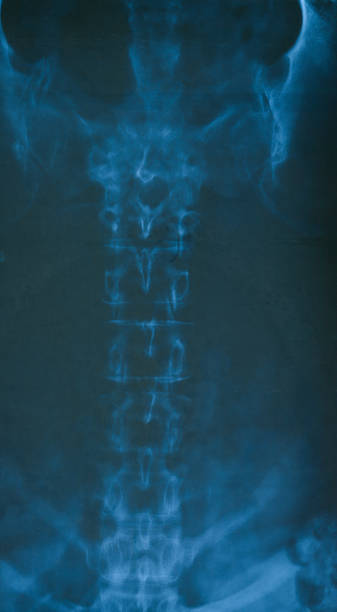

골반은 복부 하단에 위치하고 있는데 양쪽의 2개 볼기뼈와 후단부의 천골(엉치뼈)와 미골(꼬리뼈)로 구성되어 있으며 척추 부분과 하지를 연결하여 체중을 지탱하며 각종 내장과 자궁, 난소, 방광 등 주요 장기를 외부 충격에서 보호할 수 있습니다.

골반 통증 원인 2. 천장관절증후군

골반 통증 원인 두 번째는 천장관절증후군입니다. 천장관절 증후군 역시 허리디스크와 비슷한 통증으로 오인을 받을 수 있는데 천장관절 주변에 위치한 인대 손상, 관절의 불균형과 불안정성 대문에 허리와 엉덩이 주변으로 각종 통증이 생기는 질환을 의미합니다.

처장관절은 천골(엉치뼈), 장골(엉덩이뼈)가 만나는 부위로 외부 충격 혹은 골반이 힘을 주며 불편한 자세로 일어나거나 한쪽으로 체중이 쏠리는 잘못된 자세로 인하여 천장관절 주변으로 조직이나 인대 등에서 통증을 유발하는데 심할 경우 계단 오르내리는 것 자체도 어려워 질 수 있습니다.